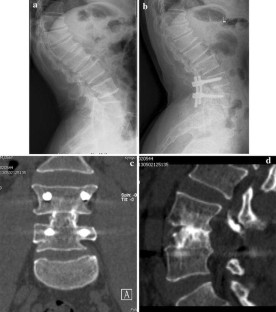

Fig. 1